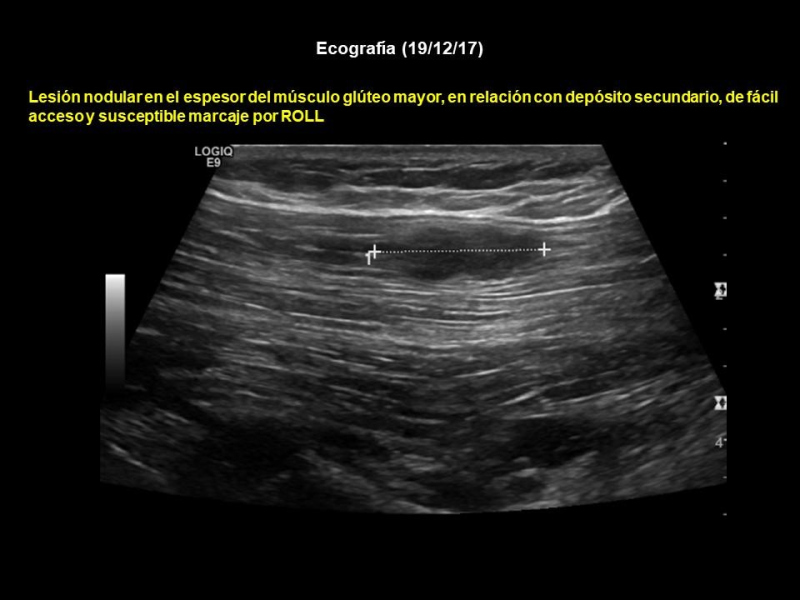

Se realiza PET-CT (7/12/17) previo a resección de adenopatía inguinal izquierda (Figs. 3 y 4), hallándose lesión focal de 14 mm con incremento de actividad metabólica (SUV 8,3) situada a nivel del músculo glúteo mayor izquierdo sugestivo de implante secundario, sin traducción morfológica en CT. Además, adenopatía inguinal izquierda con incremento de la actividad metabólica (17mm/SUV 4) compatible con posibles cambios inflamatorios secundarios a punción reciente. Una nueva ecografía muestra lesión nodular en el espesor del músculo glúteo mayor, en relación con depósito secundario, de fácil acceso y susceptible de marcaje por ROLL (Fig. 5). También se encuentran dos adenopatías inguinales izquierdas, con criterios de posible secundarismo ganglionar.